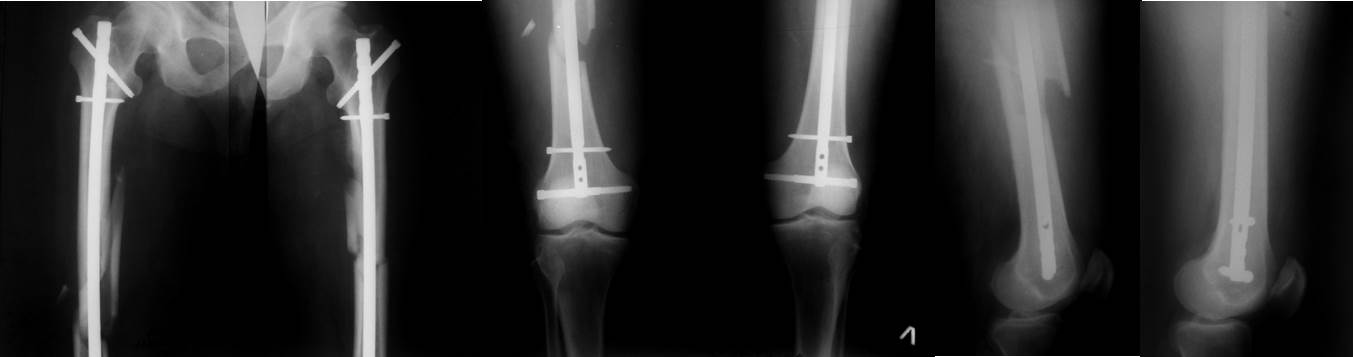

дела - пример из личной практики трёхнедельной давности. Переломы обеих

бёдер фиксированы стержнями той же фирмы, что и в обсуждаемом случае.

Остеосинтез обоих бёдер выполнен за одну операцию продолжительностью 2

часа 40 минут. Положение больного на боку на обычном хирургическом

столе. Репозиция отломков в«custom-made»  спицевом  репозиционном

аппарате  на двух спицах с корректором угловых деформаций. Определение

точки ввода и проведение спицы, как правило,  с первой попытки  с

помощью«custom-made»  прицельного устройства. Рентгеновский снимок

только для подтверждения расположения спицы.  Ни на одном этапе операции

режим прямой флюроскопии не используется. Введение стержня на уже

репонированном переломе.  Самое дистальное отверстие в стержне

предварительно до операции рассверлено до диаметра 6,55 мм и при

дистальном блокировании в  него вводится по предварительно проведенной

спице канюлированный блокирующий винт  диаметром 6,5 мм той же фирмы.

Введением  такого винта решается сразу три задачи. Во-первых,

исключается«шат»  во фронтальной плоскости, поскольку разница между

диаметром отверстия и диаметром винта всего 0,05 мм и во-вторых,

отпадает необходимость во введении винта в сагитальной плоскости, и

в-третьих, он способен без проблем держать нагрузку при ходьбе.

Дистальное блокирование с помощью«custom-made»  механического

прицельного устройства, не требующего не только режима прямой

флюроскопии, но и вообще рентгенологического подтверждения попадания

блокирующих винтов, что значительно сокращает время вмешательства.

Соответствующее дистальному и проксимальное блокирование,  чтобы

обеспечить больному сразу полную нагрузку на ноги.  Вертикализация

больного на пятые сутки после операции, контрольная рентгенограмма,

которую вы видите, на двенадцатые сутки перед выпиской. Больной был уже

неделю на ногах.  Понимаю, что у каждого доктора свой опыт и